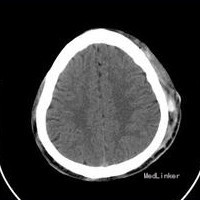

查体:Bp:160/100mmHg,左后头部见一大小约4*5CM大小血肿,双侧瞳孔等大等圆,对光反射灵敏,双侧眼球活动自如,无震颤,鼻部有淤痕,双侧鼻唇沟对称,伸舌居中。颈无抵抗,克氏征阴性,布氏征阴性。躯体浅感觉对称。四肌肌力5级,肌张力正常,病理反射未引出。 头颅CT示:左侧枕顶部皮下血肿。鼻骨骨折?鼻咽壁增厚,建议进一步检查。心电图示:正常。余结果未见异常。

诊断:1、晕厥查因:反射性晕厥? 2、高血压病 予营养支持、尼莫地平改善脑循环、及其他对症治疗等,完善其他检查,并由耳鼻喉科会诊诊治。